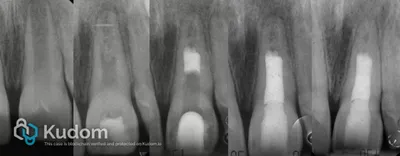

Trattamento endodontico di un primo molare mascellare, con attenzione alla corretta detersione, sagomatura e otturazione.

Rigenerazione pulpare su dente immaturo necrotico: disinfezione canalare, induzione del sanguinamento apicale con stabilizzazione del coagulo e sigillatura con plug di MTA, seguito da progressivo sviluppo radicolare.